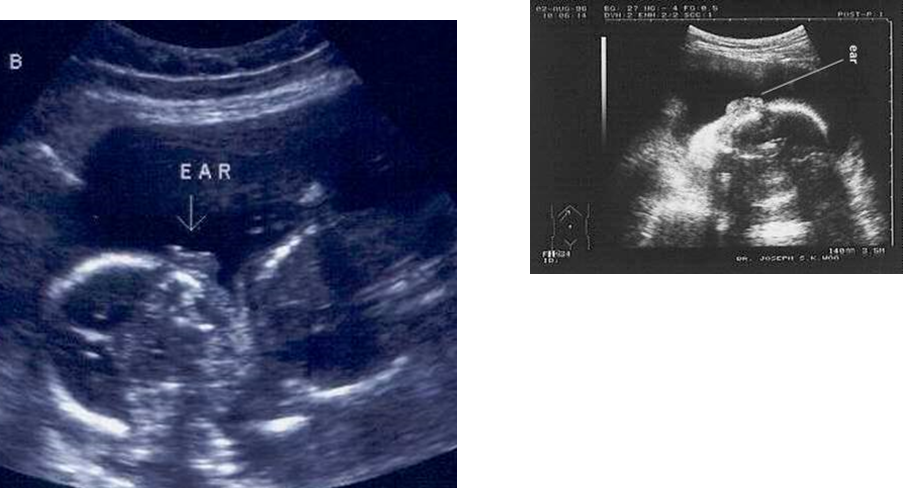

Are malformations of the ear predicted on US?

No, are rarely predicted on US

If malformations of the ear are found, what are they?

•Low-set ears

•Small ears

What are these images showing?

Fetal Ears